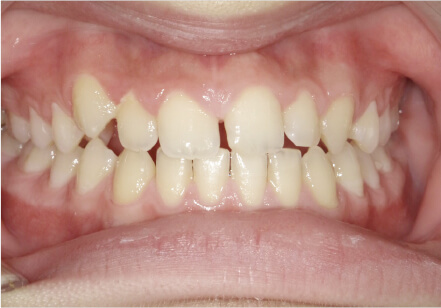

叢生の症例

17歳

女性

相談内容

カウンセリング・診断結果

治療内容・方法

全額アライナー矯正

術後の経過・現在の様子

クリアライナー使用

治療のリスク

痛み・歯根吸収・歯肉退縮・虫歯・後戻り

費用・治療期間

715,000円、2年10ヶ月